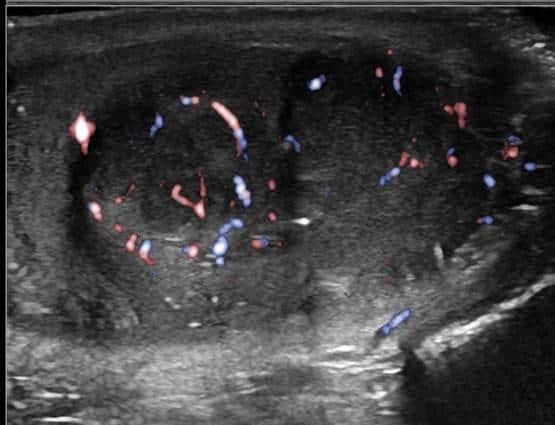

U tinh hoàn

» Thông tin: Nam giới – 28 tuổi.

» Lâm sàng: Sưng tinh hoàn.

# U tinh bào (Seminoma).